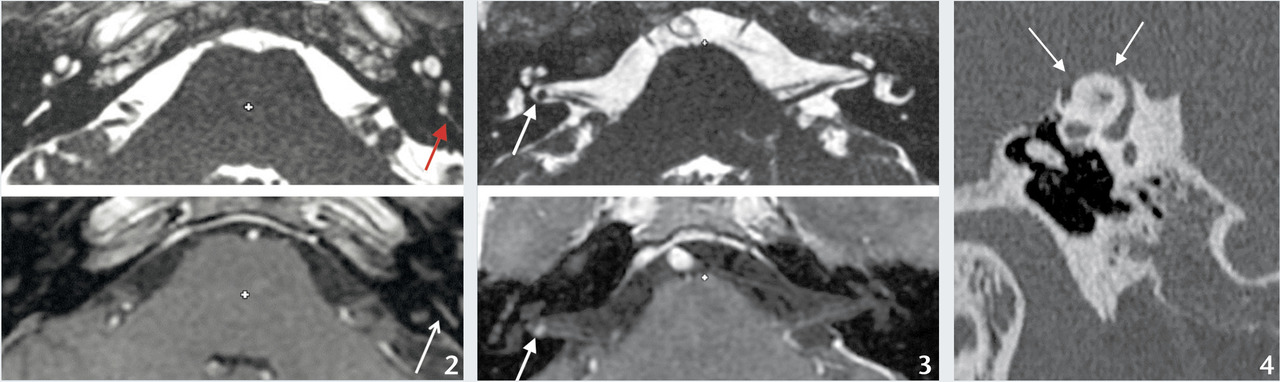

Diagnostic fourni par l’IRM :perte du signal liquidien des structures labyrinthiques et prise de contraste après injection de gadolinium (fig. 2).

À l’IRM : masse centrée sur le nerf vestibulo- cochléaire rehaussée après injection (fig. 3).

Oriente vers une pathologie de l’oreille moyenne et requiert un scanner : otite chronique (cholestéatomateuse ou non), syndrome de Minor (déhiscence du canal semi-circulaire supérieur, fig. 4), otospongiose (ostéodystrophie de la capsule labyrinthique, responsable d’une ankylose de l’étrier) ou encore fistule périlymphatique.